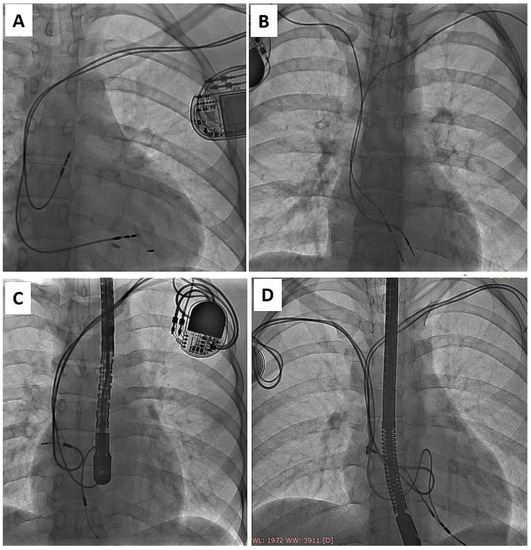

Figure 2.

Another trap of lead extraction in young adults—redundant lead slack (but planned) resulting in strong adherence to the heart structures (examples A–D). It increases the risk of targeted lead fracture, atrial wall rupture or injury to the tricuspid apparatus. Lead slack to allow for growth was supposed to prevent lead straightening, but his technique did not live up to expectations and was abandoned. (A) VVI pacing system. Old unnecessary (but made on purpose) lead loop located in RA and RVOT. (B) DDD pacing system. Proper atrial lead route and loop on ventricular lead finally located in RVOT. (C) DDD pacing system two leads, two loops (D) Another one DDD system. Proper atrial lead course and loop of ventricular lead finally located in RVOT. Presence of old models of passive leads indicates for more difficult extraction.